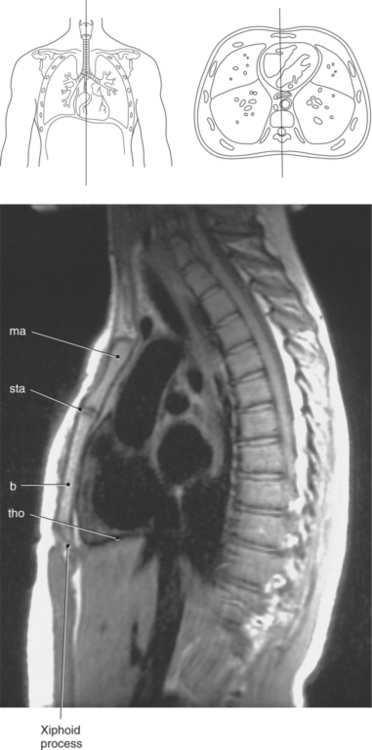

Figure 6.60 Sagittal, T1-weighted MR scan with aortic arch and descending aorta.

Key: ar, aortic arch; da, descending aorta; mbr, mainstem bronchi; rPA, right pulmonary artery; ab, aortic bulb; la, left atrium; rv, right ventricle.

Blood travels to and from the heart through the great vessels, which include the aorta, pulmonary arteries and veins, and superior and inferior venae cavae (Figures 6.54 and 6.55). The aorta is the largest artery of the body and can be divided into the ascending aorta, aortic arch, and descending aorta. The ascending aorta begins at the base of the left ventricle at the level of the sternal angle, then curves superiorly and posteriorly as the aortic arch over the root of the left lung. The top of the aortic arch is approximately at T3 (Figures 6.56 and 6.57). The arch continues as the descending aorta posterior to the left bronchus and pulmonary trunk, on the left side of the vertebral body of T4 (Figures 6.58 and 6.59). The descending aorta passes slightly anterior and to the left of the vertebral column as it descends through the thoracic and abdominal cavities (Figure 6.60). While in the thoracic cavity, the descending aorta is commonly called the thoracic aorta, and while in the abdominal cavity, it is called the abdominal aorta. The pulmonary trunk is the origin of the right and left pulmonary arteries and lies entirely within the pericardial sac. It arises from the right ventricle and ascends in front of the ascending aorta, courses posteriorly and to the left, where it bifurcates at the level of the sternal angle (T4) into the right and left pulmonary arteries (Figures 6.61 through 6.63). The pulmonary trunk is attached to the aortic arch by a fibrous cord called the ligamentum arteriosum, the remnant of an important fetal blood vessel (ductus arteriosus) that links the pulmonary and systemic circuits during fetal development (Figures 6.54 and 6.61). The right pulmonary artery courses laterally, posterior to the ascending aorta and superior vena cava, and anterior to the esophagus and right mainstem bronchus, to the hilum of the right lung. At the root of the right lung, the right pulmonary artery divides into two branches, with the lower branch supplying the middle and inferior lobes and the upper branch supplying the superior lobe (Figures 6.61 through 6.64). The left pulmonary artery, shorter and smaller than the right, is also the most superior of the pulmonary vessels. It travels horizontally, arching over the left mainstem bronchus, and enters the hilum of the left lung just superior to the left mainstem bronchus (Figures 6.61 through 6.64). Within the lungs, each pulmonary artery descends posterolateral to the main bronchus and divides into lobar and segmental arteries, continuing to branch out and to follow along with the smallest divisions of the bronchial tree (Figures 6.61 and 6.64). Located inferior to the pulmonary arteries are the four pulmonary veins, two each (superior and inferior) extending from each lung to enter the left atrium (Figures 6.54, 6.55, 6.61, and 6.64 through 6.68). They commence in a capillary network along the walls of the alveoli, where they are continuous with the capillaries of the pulmonary arteries. The venous capillaries merge to form small vessels that unite successively to eventually form a single trunk for each lobe: three for the right and two for the left lung. Frequently the trunk from the middle lobe of the right lung unites with the trunk from the upper lobe, forming just two trunks on the right side prior to entering the left atrium. The right superior pulmonary vein collects blood from the upper lobe segments of the right lung and passes anterior and inferior to the right pulmonary artery, behind the superior vena cava. The right inferior pulmonary vein receives blood from the right lower lobes of the lung and crosses behind the right atrium to the left atrium (Figures 6.61 and 6.69 through 6.71). The left superior pulmonary vein receives blood from the left upper lobe of the left lung and courses anterior and inferior to the left main bronchus as it enters the left atrium. The left inferior pulmonary vein drains the inferior lobe of the left lung and passes toward the left atrium anterior to the bronchi (Figures 6.61 and 6.72 through 6.74). The pulmonary veins course more horizontally than the pulmonary arteries and are ultimately oriented toward the left atrium. At the root of the lungs, the pulmonary veins are anterior to the pulmonary arteries, which are anterior to the bronchus. While within the lungs, the branches of the pulmonary arteries are anterior to the bronchi, which are anterior to the pulmonary veins. The superior and inferior venae cavae are the largest veins of the body. The superior vena cava is formed by the junction of the brachiocephalic veins, posterior to the right first costal cartilage, and carries blood from the thorax, upper limbs, head, and neck (Figure 6.24). As it travels inferiorly, it is located posterior and lateral to the ascending aorta before entering the upper portion of the right atrium (Figures 6.54 through 6.59). The inferior vena cava is formed by the junction of the common iliac veins in the pelvis and ascends the abdomen to the right of the abdominal aorta and anterior to the vertebral column. It passes through the caval hiatus of the diaphragm and almost immediately enters the inferior portion of the right atrium (Figures 6.75 and 6.76).